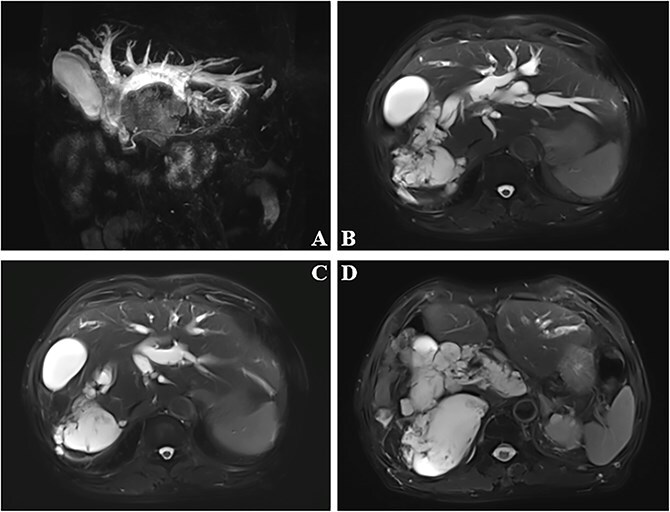

Mucinous cholangiocarcinoma is a rare, aggressive biliary tract malignancy. Excessive mucin secretion causes diagnostic and therapeutic challenges. A 76-year-old male presented with painless progressive jaundice. Imaging showed cystic lesions with calcification in the right liver/hilum, intrahepatic bile duct dilation, and stones. Radical resection was deemed unfeasible due to insufficient predicted residual liver volume. Given the high risk of mucin-induced obstruction with conventional biliary drainage, palliative choledochojejunostomy was performed. Intraoperative findings revealed mucin and stones; frozen section pathology confirmed biliary mucinous adenocarcinoma. Postoperatively, bilirubin decreased significantly and biliary dilation improved. Mucinous cholangiocarcinoma management requires a multidisciplinary approach. When radical resection is contraindicated, palliative choledochojejunostomy effectively relieves mucin-related obstruction. Long-term outcomes depend on adjuvant therapy and surveillance; further, molecular research is needed to develop targeted therapies.